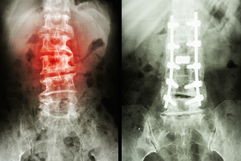

Para determinar la causa del dolor en las piernas, el médico evalúa la curvatura de la columna y las extremidades óseas. También puede realizar maniobras para provocar el dolor y palpar el abdomen, con el fin de comprobar si existe dolor en la región abdominal o pélvica.

Además, pueden solicitarse análisis de sangre, estudio del líquido sinovial y pruebas de imagen, como radiografía o resonancia magnética. A partir de los resultados, es posible establecer el diagnóstico e indicar el tratamiento más adecuado en cada caso.

4. Alteraciones de la columna

Cuando el dolor en las piernas se agrava con el movimiento de la columna podría ser causado por lesiones a nivel de las vértebras.

La estenosis del canal vertebral puede causar dolor moderado o intenso, así como sensación de peso o calambres en la región lumbar, glúteos, muslos y en las piernas al caminar.

En estos casos el dolor sólo se alivia al sentarse o al inclinar el cuerpo hacia adelante, podría estar presente una sensación de adormecimiento.

La espondilolistesis también es una posible causa de dolor en la espalda inferior que se irradia hacia los glúteos y las piernas, además de esto también suele haber rigidez muscular y contracturas, este dolor suele aliviarse durante el reposo.

La hernia discal también causa dolor en la espalda que se irradia hacia los glúteos y las piernas, e inclusive extenderse hasta el tobillo y la planta del pie, este dolor suele ser agudo e intenso.

Qué hacer: colocar una compresa tibia en el lugar del dolor puede aliviar los síntomas, sin embargo, el médico puede recomendar la ingesta de antiinflamatorios y la realización de fisioterapia.